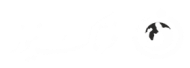

در جریان آزمایشها، محققان توانستند با استفاده از این فرآیند ۸۲ تخمک سالم را تولید کنند که سپس در آزمایشگاه بارور شدند. تقریباً ۹ درصد از این تخمکها به مرحله بلاستوسیست (مرحله خاصی از رشد جنین) رسیدند. با این حال، محققان بلاستوسیستها را پس از این مرحله کشت ندادند که این زمان مصادف با زمانی است که معمولاً در درمان IVF به رحم منتقل میشوند.